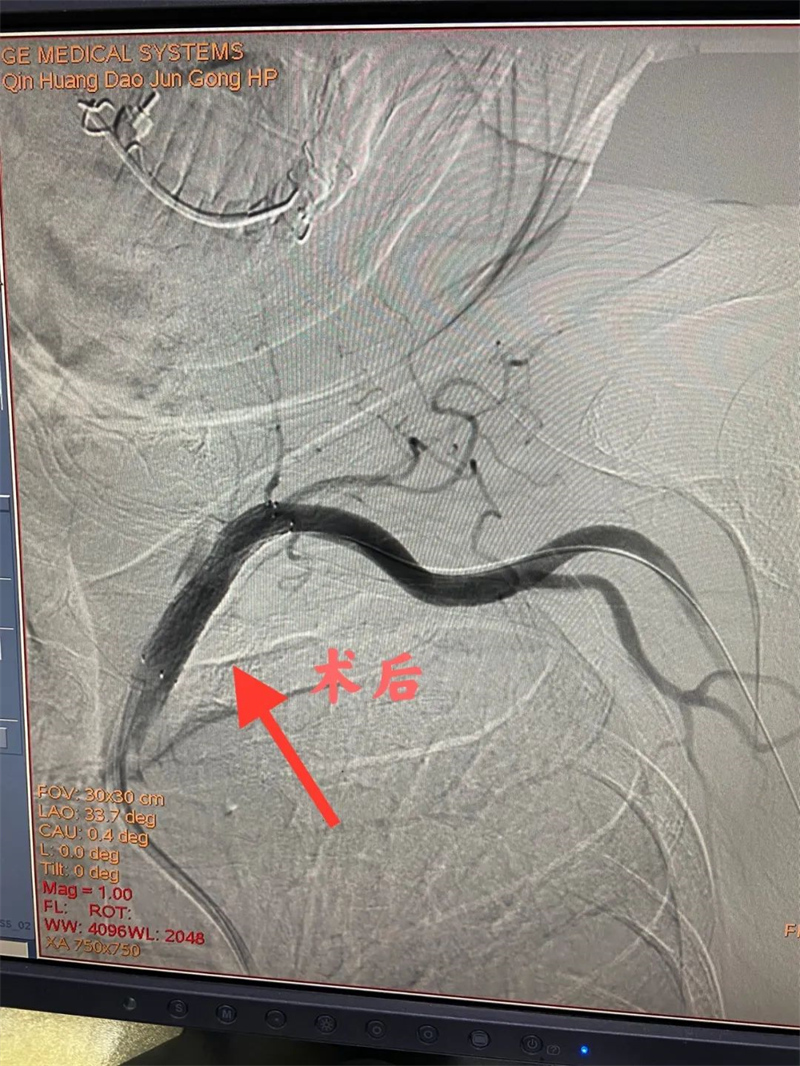

经过充分的准备后,心血管内二科及神经血管介入科团队通过股动脉穿刺,为患者顺利完成冠状动脉造影、肾动脉造影及左侧锁骨下动脉造影。冠状动脉造影结果提示患者前降支远段70%狭窄,确诊为冠状动脉粥样硬化性心脏病。肾动脉造影提示左侧肾动脉起始段中度狭窄,明确了肾动脉狭窄。左侧锁骨下动脉造影提示起始段次全闭塞。成功植入两枚支架,术后患者头晕缓解,左侧桡动脉搏动有力。